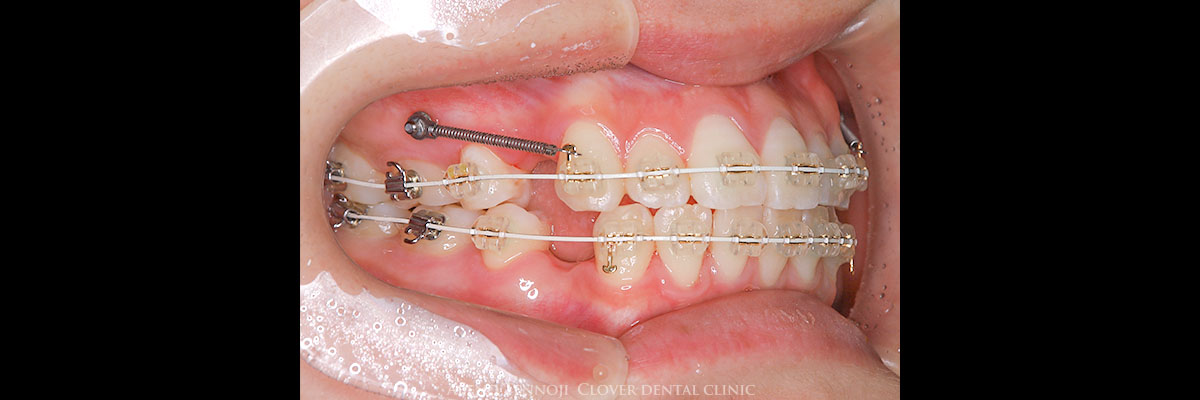

歯の表側にワイヤーを装着して歯並びを治す一般的な矯正方法です。

歯の表面にブラケットを付けて、そこへワイヤーを通して少しずつ歯を動かしていきます。